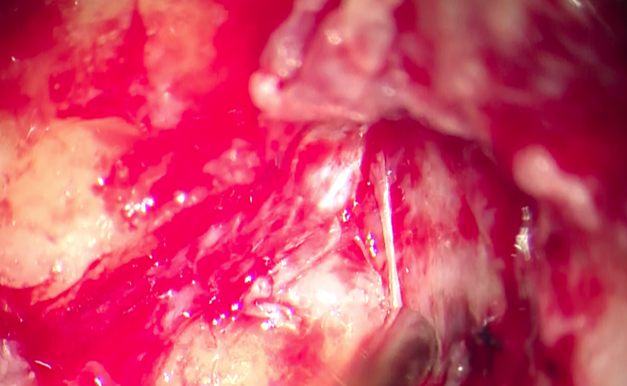

Figure 3. Operative image showing the extension of the

cholesteatoma and erosion of the mastoid and middle ear structures.

Figure 4. Operative image

showing the erosion of the fallopian canal and the facial nerve

Figure 5. Operative image showing invading the carotid canal

and jugular gulf.